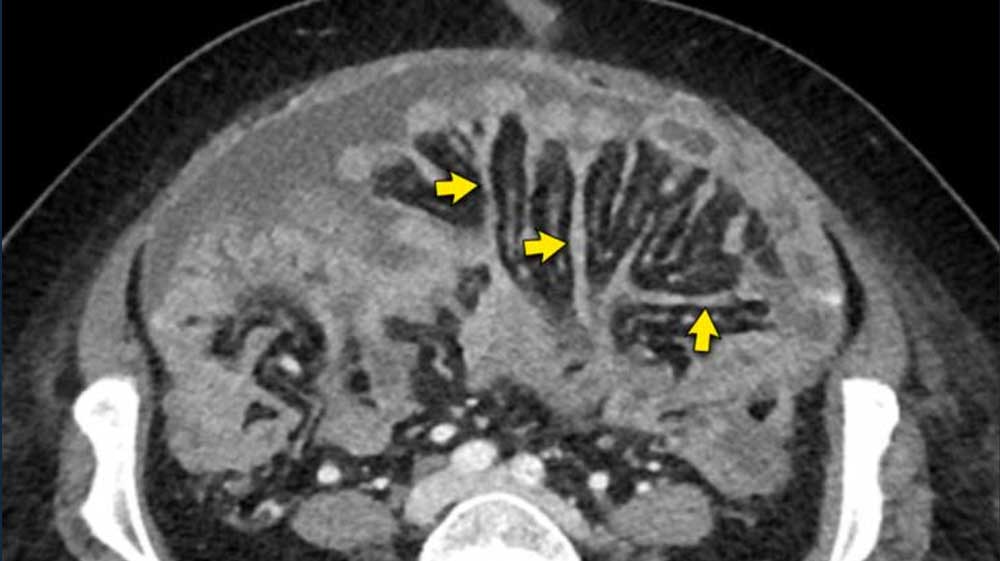

Peritoneal Carcinomatosis